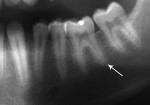

Five cases met the criteria as set forth in the study and are summarized in Table 1; radiographs of the five cases are shown in Figure 1 through Figure 21. Ages ranged from 15 to 48 years. Four patients were male and one female. All five cases involved Caucasian patients. Two cases involved the distal roots of mandibular first molars bilaterally (Figure 1, Figure 2, Figure 3, Figure 4, Figure 5, Figure 6, Figure 7, Figure 8, and Figure 18, Figure 19, Figure 20, and Figure 21); one case involved both roots of the mandibular first molars bilaterally (Figure 11, Figure 12, Figure 13, Figure 14); and two cases involved the mandibular second premolar unilaterally (Figure 9 and Figure 10, and Figure 15, Figure 16, and Figure 17). Two of the patients presented with symptoms similar to cracked-tooth syndrome (Table 1, Case 3 and Case 4), one with “chronic reversible pulpitis” (Table 1, Case 1), and two were asymptomatic (Table 1, Case 2 and Case 5).

Patients in all five cases exhibited PARR of the involved roots, as previously described (Figure 1 through Figure 21).40 The roots showed shortening and blunting of the apex of greater than 2 mm in all five cases. In three of the five cases, the PARR self-arrested without any treatment. The mandibular left first molar in Case 1 (Figure 5, Figure 6, Figure 7, and Figure 8) received conventional root canal therapy (RCT), while the mandibular right first molar in Case 3 (Figure 11, Figure 12, Figure 13, Figure 14) received a bonded ceramic crown. The PARR appears to have arrested in these two cases, and the outcome of the treatment in relation to the resorption could not be determined. The symptoms the patients were experiencing did eventually resolve. Consequently, all five study cases became symptom-free, including the patient who received conventional RCT (Case 1).

The Case 1 patient, who was the son of the Case 2 patient, was observed in preoperative orthodontic records prior to initiating orthodontic therapy (Figure 1 and Figure 2). The Case 1 patient also demonstrated PARR of the mandibular anterior incisors post-orthodontic therapy (Figure 8). The Case 5 patient had serial extractions completed as a child, but no fixed or removable orthodontic appliances were utilized. Past medical histories were all noncontributory (Table 1). No cases of MICR or MIAR were identified in any of the files reviewed.

The radiologic feature of PARR is characteristic of LIAR. PARR was readily apparent in all five cases (Figure 1 through Figure 21). Two or more millimeters of apical root were resorbed and replaced with normal-appearing trabeculated bone. The PDL space and remnants of the lamina dura appeared to be intact. The apical root canal space appeared patent but somewhat narrowed. The teeth were not ankylosed. Conversely, PARR due to trauma results in ankylosis with bone replacement resorption from both the apical and lateral directions of the root with obliteration of the root canal space and PDL space.1,40-42 PARR from orthodontics would be impossible to distinguish from LIAR radiographically; however, a history of prior orthodontics and the location of the involved teeth would separate this process from LIAR (Table 2).